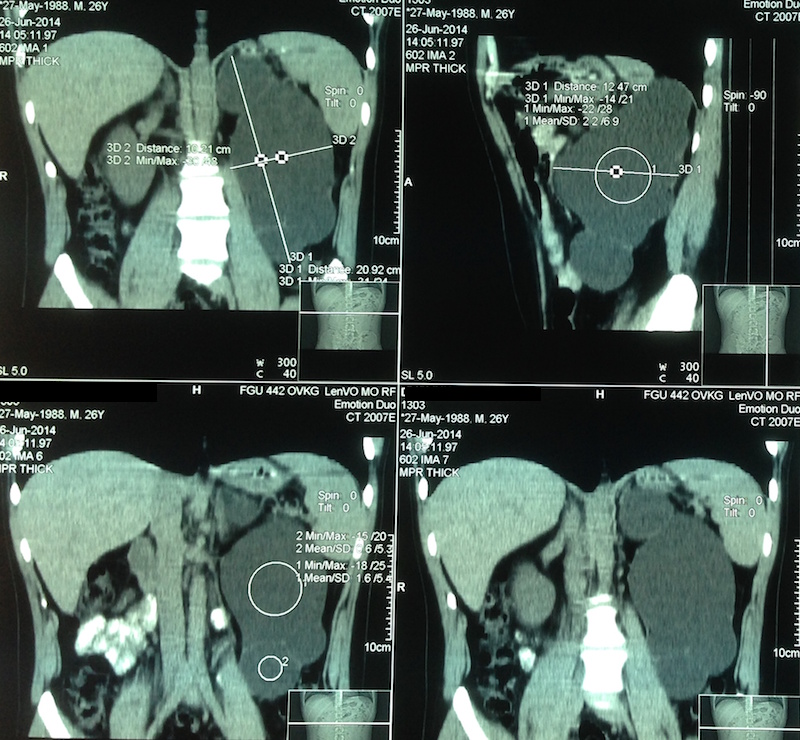

Одним из методов диагностики и выявления гидронефроза является ультразвуковое исследование. При начальных стадиях выявляется расширение лоханки и чашечек, закругление форниксов. На ультразвуковых сканах отмечается гидронефротическая трансформация почек, отмечается расширение чашечно-лоханочной системы, истончение паренхимы почек.

Обзорная рентгенограмма дает возможность определить размеры почек и обнаружить камни, если они имеются. На серии экскреторных (внутривенных) урограмм можно отметить замедленное накопление контрастного раствора в расширенных лоханке (лоханках) и чашечках. На урограммах видны расширенная, округлой формы лоханка, расширенные чашечки. При значительном нарушении функции почки контрастный раствор может накопиться в достаточной концентрации лишь через 1—2 ч или вовсе не выделиться больной почкой.

Таким образом, внутривенная урография позволяет диагностировать и стадию заболевания от пиелоэзктазии до гигантского гидронефроза со значительным снижением функции почки. Ретроградная уретеропиелография определяет причину гидронефроза, уровень локализации препятствия, его протяженность, степень расширения чашечек и лоханки почки. Антеградная пиелография показана при сомнительных данных экскреторной урографии и невыполнимости ретроградной пиелографии в связи с непреодолимым препятствием в мочеточнике. Она позволяет определить степень увеличения лоханки, уровень расположения препятствия и резорбтивную активность оставшейся паренхимы (при сохранении резорбции через 20 мин после введения контраста в расширенную лоханку удается получить экскреторную урограмму с контралатеральной стороны).